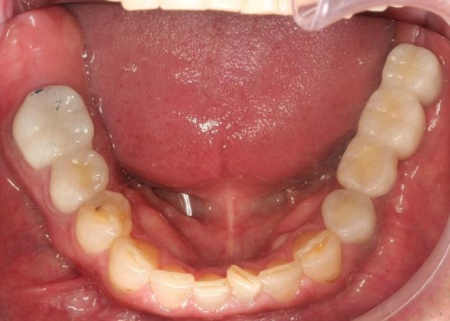

拝見したところ、右上奥歯4本が欠損しており、その影響で全体の噛み合わせのバランスが崩れていました。

欠損部が多い状態が長期間続いたことで噛み合わせが低く、新しい歯を入れるための高さも不足していました。

他院で治療を行った左下奥歯3本のインプラントは、土台をそのまま活かして人工歯だけ作り直し、噛み合わせを調整します。

左下奥歯1本、右下奥歯2本に装着されていた古い被せ物はすべて外し、ジルコニアクラウンと交換しました。

最後に、見た目や噛み合わせに問題がないかを確認し、治療を終了しています。